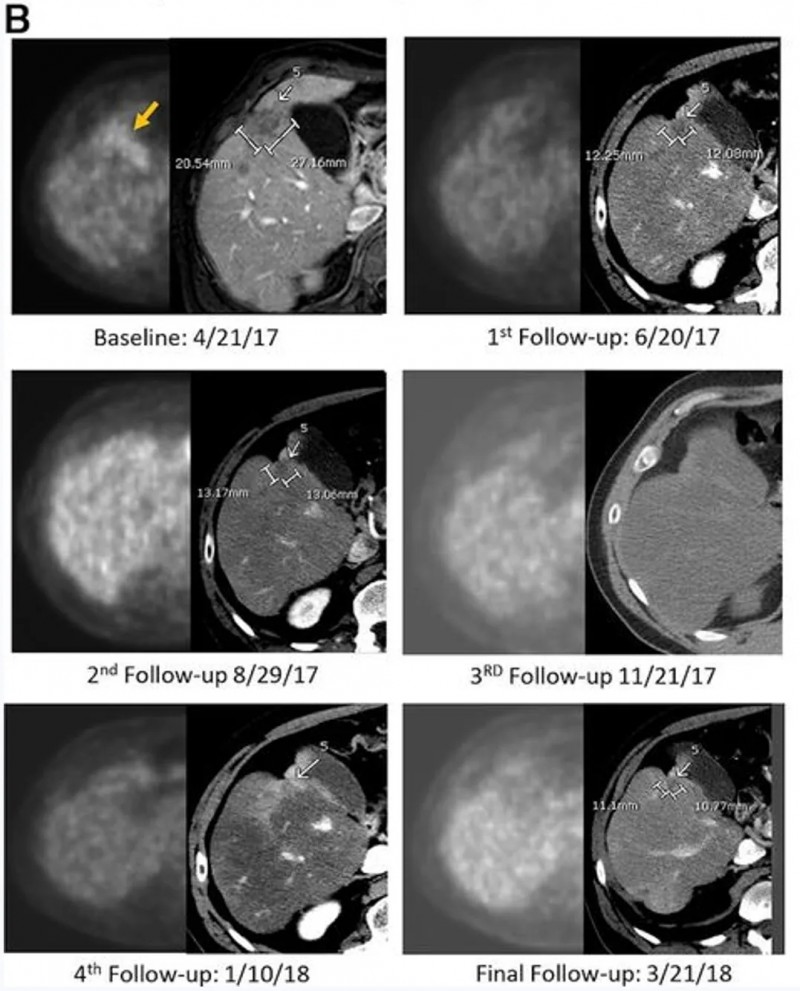

结果显示:接受CAR-GPC3T细胞治疗6个月后,影像学检查提示肿瘤迹象消失(详见下图),肿瘤标志物甲胎蛋白(AFP)也恢复正常。更令人振奋的是,截至2023年8月,该患者已无癌生存8年(始于2015年7月),并逐步回归了正常生活。

▲图源“Cancer Commun”,版权归原作者所有,如无意中侵犯了知识产权,请联系我们删除